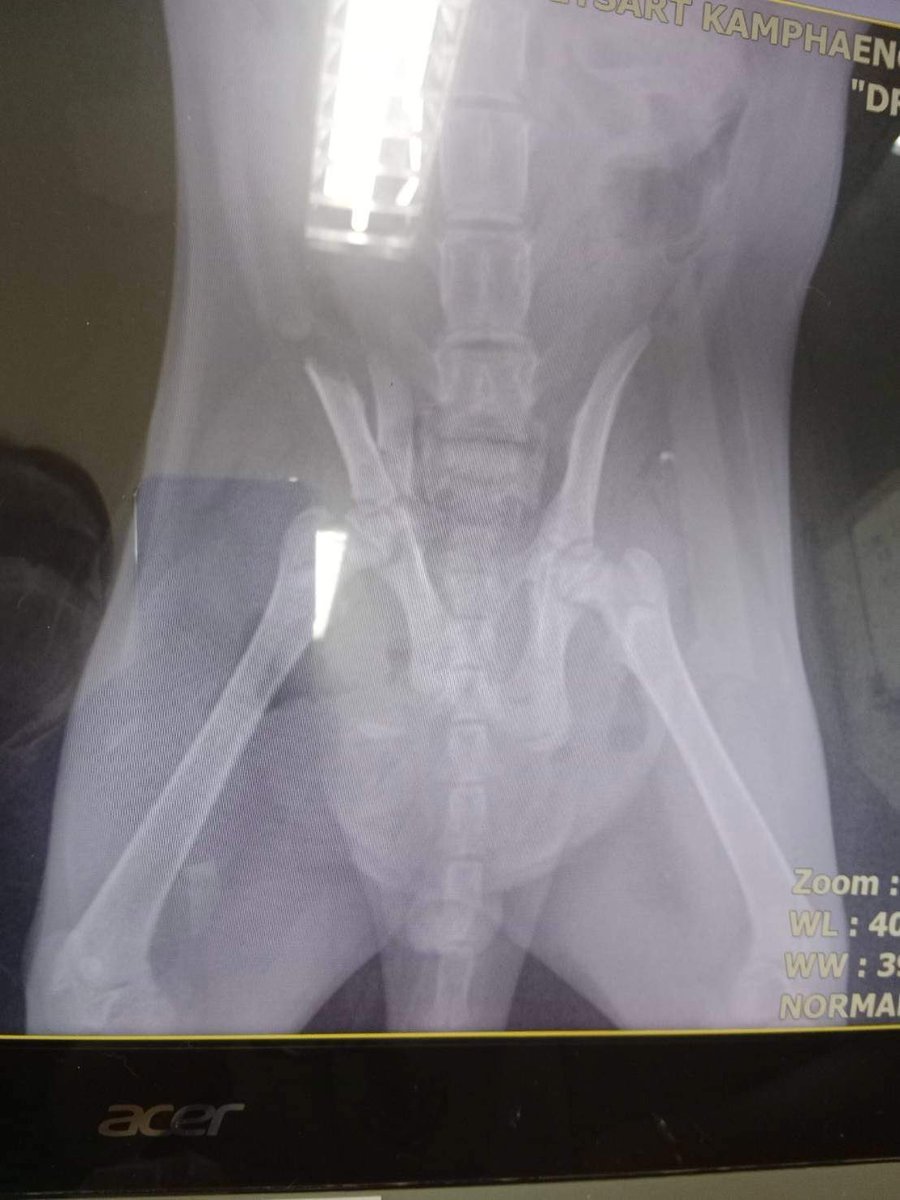

🩸หาเลือดแมว🩸 น้องอั่งเปา พันธ์ไทย อายุ 3 เดือนครึ่ง ถูกหมาใหญ่กัด ได้รับการผ่าตัดเรียบร้อย แต่หลังผ่าตัด-เกล็ดเม็ดเลือดแดงต่ำ ณ วันนี้ 15-17 (19 พ.ค.65) จึงขอความเมตตาจากท่านเจ้าของแมวที่พร้อมให้ความช่วยเหลือ ครับ พิกัด : รพส.เกษตร ติดต่อ : คุณสมศักดิ์ 088-443-8836